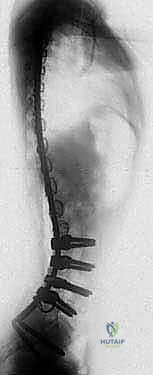

3. The curve patterns of neuromuscular scoliosis are most commonly lumbar or thoracolumbar with associated pelvic obliquity (

FIG 1

).

FIG 1•

Typical neuromuscular curve pattern in a child with quadriplegic-pattern cerebral palsy.

A.

Radiograph of long thoracolumbar curve with pelvic obliquity.

B.

Clinical picture of this child with poor sitting balance.